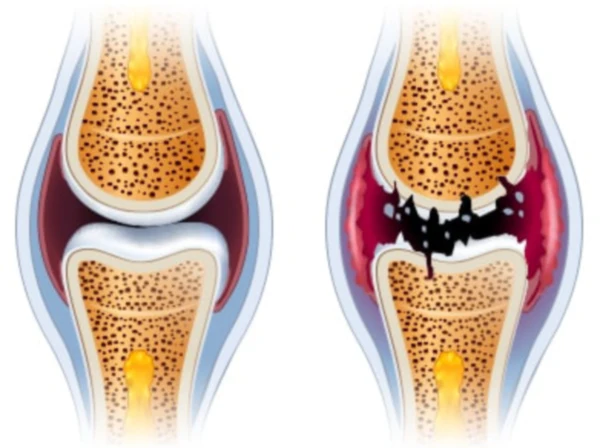

통풍이란 요산이 체내에 쌓여 관절에 염증을 일으키는 질병으로, 관절이 혹처럼 튀어나와 보일 정도로 심한 증상을 유발한다. 통풍이라 불리는 이 질병은 고통스럽고 찌르는 통증을 동반하며, 바람이 불면 더욱 심해지는 것이 특징이다. 이러한 고통은 주로 밤이나 새벽에 나타나며, 급성인 경우 일주일에서 한 달 동안 지속될 수 있다. 만성적인 경우에는 요산배설촉진제를 사용하여 치료된다.

통풍은 주로 체내에 과다 축적된 요산으로 인해 발생합니다. 요산은 우리가 섭취하는 다양한 음식이 소화되어 최종적으로 대사된 후 혈액에 녹아 있다가 소변으로 배출되는 물질입니다. 일반적으로 혈액 내에서 요산은 정상 수준을 유지하며 배설됩니다. 그러나 통풍 환자는 혈액 내 요산이 과다하게 증가합니다. 이러한 과다 축적된 요산은 결정체로 변화하고, 이러한 결정체가 관절 내에 침착하여 염증을 일으킵니다.

통풍을 적절히 치료하지 않을 경우, 발작성 관절염의 빈도가 증가하고 침범하는 관절 수도 더 많아지며, 회복에 필요한 시간도 증가합니다. 반복적인 관절염은 관절을 점차 손상시키며, 만성적인 관절염으로 진행될 수 있습니다. 또한 통풍성 결절이라 불리는 덩어리가 관절 주위나 피부 조직에 나타날 수 있습니다. 이러한 결절은 요산 결정체의 덩어리로 어느 부분에서든 형성될 수 있으며, 주로 팔꿈치, 귀, 손가락, 발가락, 발목 등에서 발생할 수 있습니다. 때로는 요로 결석을 형성하기도 합니다.